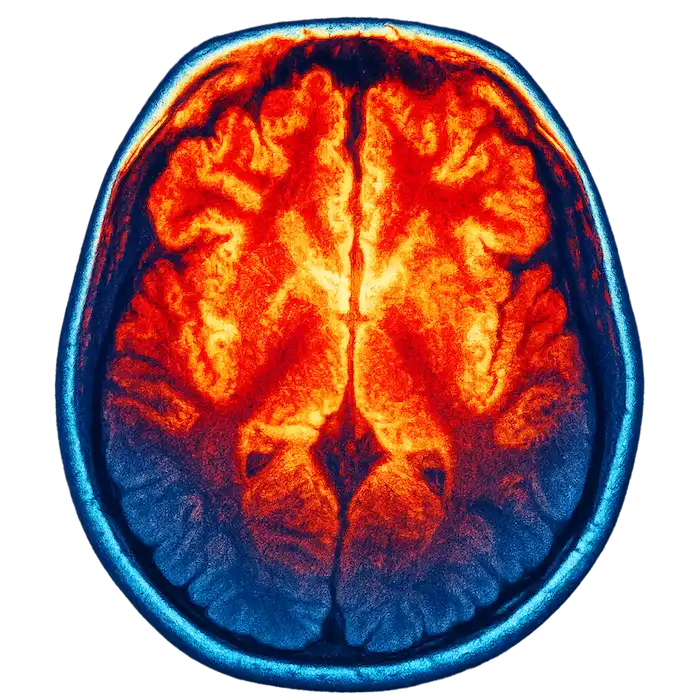

Brainwave Analysis

Your brain’s electrical patterns don’t lie. They reveal your true stress levels regardless of what’s happening with your heart rate.

Even when HRV appears normal, brainwave analysis often picks up on underlying stress that isn’t showing up elsewhere. It catches what the HRV assessment might miss—the tension your body has learned to hide or compensate for.

Together, these two assessments give us a complete picture. If stress is affecting your nervous system, we’ll find it.

Brain scan colorized for effect